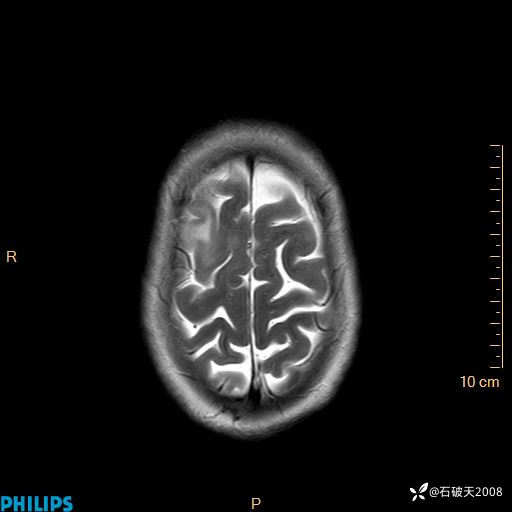

2020.11.14MR

T2